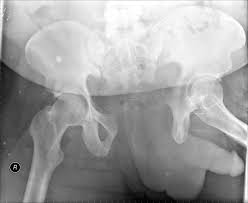

A 35 year-old female presents after prolonged extrication from a motor vehicle collision complaining of severe pelvic pain. Physical examination reveals diminished perianal sensation. She is otherwise neurologically intact. Figures A through D are radiographs and representative CT cuts of her injury. Which of the following nerve roots has likely been injured by the acute trauma?

The clinical scenario is consistent with a high-energy sacral fracture. The radiographs in figures A and B demonstrate a sacral fracture with posterior displacement of the right hemipelvis seen on the inlet view. Figures C and D are axial and sagittal CT images which show a displaced fracture of the right

hemisacrum along with a transvere fracture component through the S3 body . Diminished perianal sensation is concerning for an S2 nerve root injury.

Mehta et al reviewed the current management of sacral fractures. They note that the S1 and S2 nerve roots are more likely to be injured with sacral fractures as they occupy 1/3 to 1/4 of the neural foramina, as opposed to S3 and S4, which only occupy 1/6 of the neural foramina.

Robles reviewed the current literature to ascertain principles of evaluation and treatment for transverse sacral fractures. The author notes that injury to nerve roots S2 to S5 is manifested by impairment of urinary and anal continence and sexual function.

The first illustration demonstrates the sacral nerve root dermatomal distribution. The second shows a pelvic cadaver dissection demonstrating the sacral nerve roots as they exit the foramina.